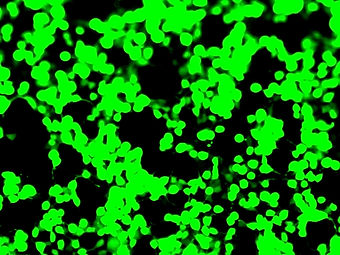

Persistence of an intact HIV reservoir in phenotypically naive T cells

Abstract: Despite the efficacy of antiretroviral therapy (ART), HIV persists in a latent form and remains a hurdle to eradication. CD4+ T lymphocytes harbor the majority of the HIV reservoir, but the role of individual subsets remains unclear. CD4+ T cells were sorted into central, transitional, effector memory, and naive T cells. We measured HIV DNA and performed proviral sequencing of more than 1900 proviruses in 2 subjects at 2 and 9 years after ART initiation to estimate the contribution of each subset to the reservoir. Although our study was limited to 2 subjects, we obtained comparable findings with publicly available sequences. While the HIV integration levels were lower in naive compared with memory T cells, naive cells were a major contributor to the intact proviral reservoir. Notably, proviral sequences isolated from naive cells appeared to be unique, while those retrieved from effector memory cells were mainly clonal. The number of clones increased as cells differentiated from a naive to an effector memory phenotype, suggesting naive cells repopulate the effector memory reservoir as previously shown for central memory cells. Naive T cells contribute substantially to the intact HIV reservoir and represent a significant hurdle for HIV eradication.